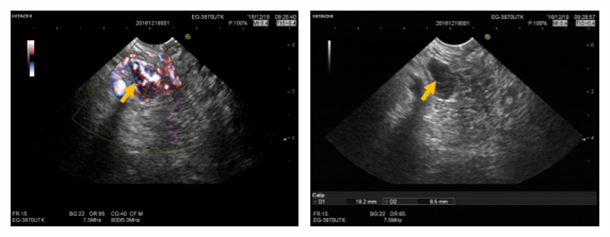

首次超声内镜检查:病变位于胰头近钩突位置,截面椭圆形血供丰富。

2016.12.22.行FNA穿刺活检与无水乙醇消融术,将穿刺针准确刺入。病变内留取样本送检,超声监控下注射无水乙醇1.6ml。